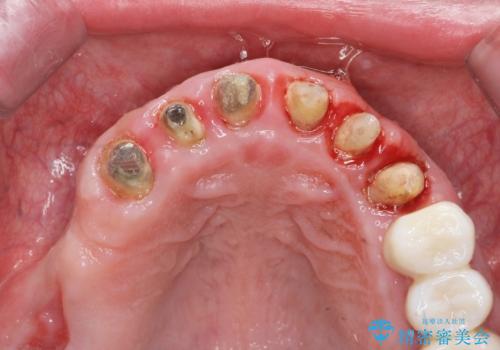

- 「セラミック治療を他院で受けたが、それ以来歯ぐきが腫れ違和感がある、改善してほしい。」と歯ぐきの状態改善を希望され来院されました。

歯周組織検査を行うと歯ぐきからは容易に出血し、X線検査より歯とセラミッククラウンの適合が悪い(ピッタリと合っていない)状態が示唆され、歯ぐきの炎症を惹起している状態でした。

セラミッククラウンを除去し仮歯を装着し、歯周外科手術を行い歯ぐきの状態を改善したのち、適合の良いセラミッククラウンを再作製をする治療計画としました。